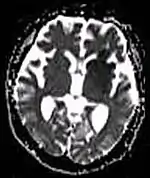

| Diffusion weighted (DWI) | Conventional | DWI | Measure of Brownian motion of water molecules.[17] | High signal within minutes of cerebral infarction (pictured).[18] |  |

| Apparent diffusion coefficient | ADC | Reduced T2 weighting by taking multiple conventional DWI images with different DWI weighting, and the change corresponds to diffusion.[19] | Low signal minutes after cerebral infarction (pictured).[20] |  | |

Another application of diffusion MRI is diffusion-weighted imaging (DWI). Following an ischemic stroke, DWI is highly sensitive to the changes occurring in the lesion.[44] It is speculated that increases in restriction (barriers) to water diffusion, as a result of cytotoxic edema (cellular swelling), is responsible for the increase in signal on a DWI scan. The DWI enhancement appears within 5–10 minutes of the onset of stroke symptoms (as compared to computed tomography, which often does not detect changes of acute infarct for up to 4–6 hours) and remains for up to two weeks. Coupled with imaging of cerebral perfusion, researchers can highlight regions of "perfusion/diffusion mismatch" that may indicate regions capable of salvage by reperfusion therapy.